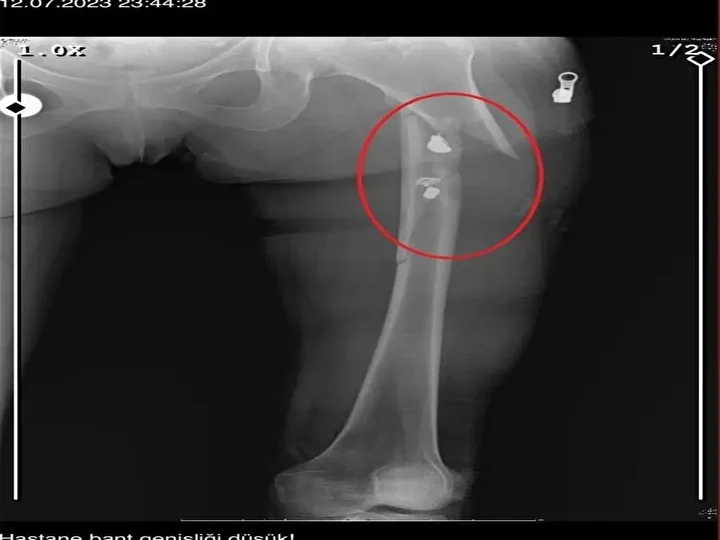

İlyas S., sevgilisi Fatma O.'yu da 8 kurşunla vurup, yaraladı. Arkadaşı Özaslan'ın cesedini önce çarşafa sonra da streç filme sarıp bantlayan İlyas S., eczaneden aldığı sargı bezi ve ilaçlarla pansumanını yaptığı sevgilisine yaralı haldeyken 21 gün boyunca cinsel saldırıda bulundu.

Fatma O., annesine yazdığı mesajda, "Odada ceset var. Telefon dinleniyor. Bana 8 el ateş etti. Yaralıyım. Polisi görürse önce beni öldürecek. Onu parayla kandırıp, evden çıkartın. Sonra da beni alın' dedi. Fatma O.’nun annesi, bu mesaj sonrası polise gidip şikayette bulundu. Polis, Fatma O.'nun annesi aracılığıyla İlyas S. ile iletişime geçti. Fatma O.'nun annesi, telefonla aradığı İlyas S'yi, kızına para götürmesi için evine çağırdı. Ekipler, parayı almaya gelen İlyas S'yi kendilerine silah çekmesine rağmen yakaladı. Eve giden ekipler, ağır yaralı haldeki Fatma O. ve kokmaya başlayan cesetle karşılaştı.